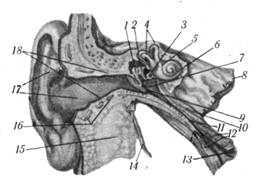

Рис. 2.7. Наружное, среднее и внутреннее ухо:

1 — молоточек; 2 — наковальня; 3 — стремя; 4 — полукружные каналы; 5 — преддверие; 6 — улитка; 7— барабанная полость; 8— каменистая часть височной кости; 9 — барабанная перепонка; 10—мышца, натягивающая барабанную перепонку; 11 — слуховая труба; 12 — хрящи слуховой трубы; 13 — глоточное отверстие слуховой трубы; 14 — шиловидный отросток; 15 — околоушная железа; 16 — хрящи наружного слухового прохода; 17 — ушная раковина; 18 — наружный слуховой проход.